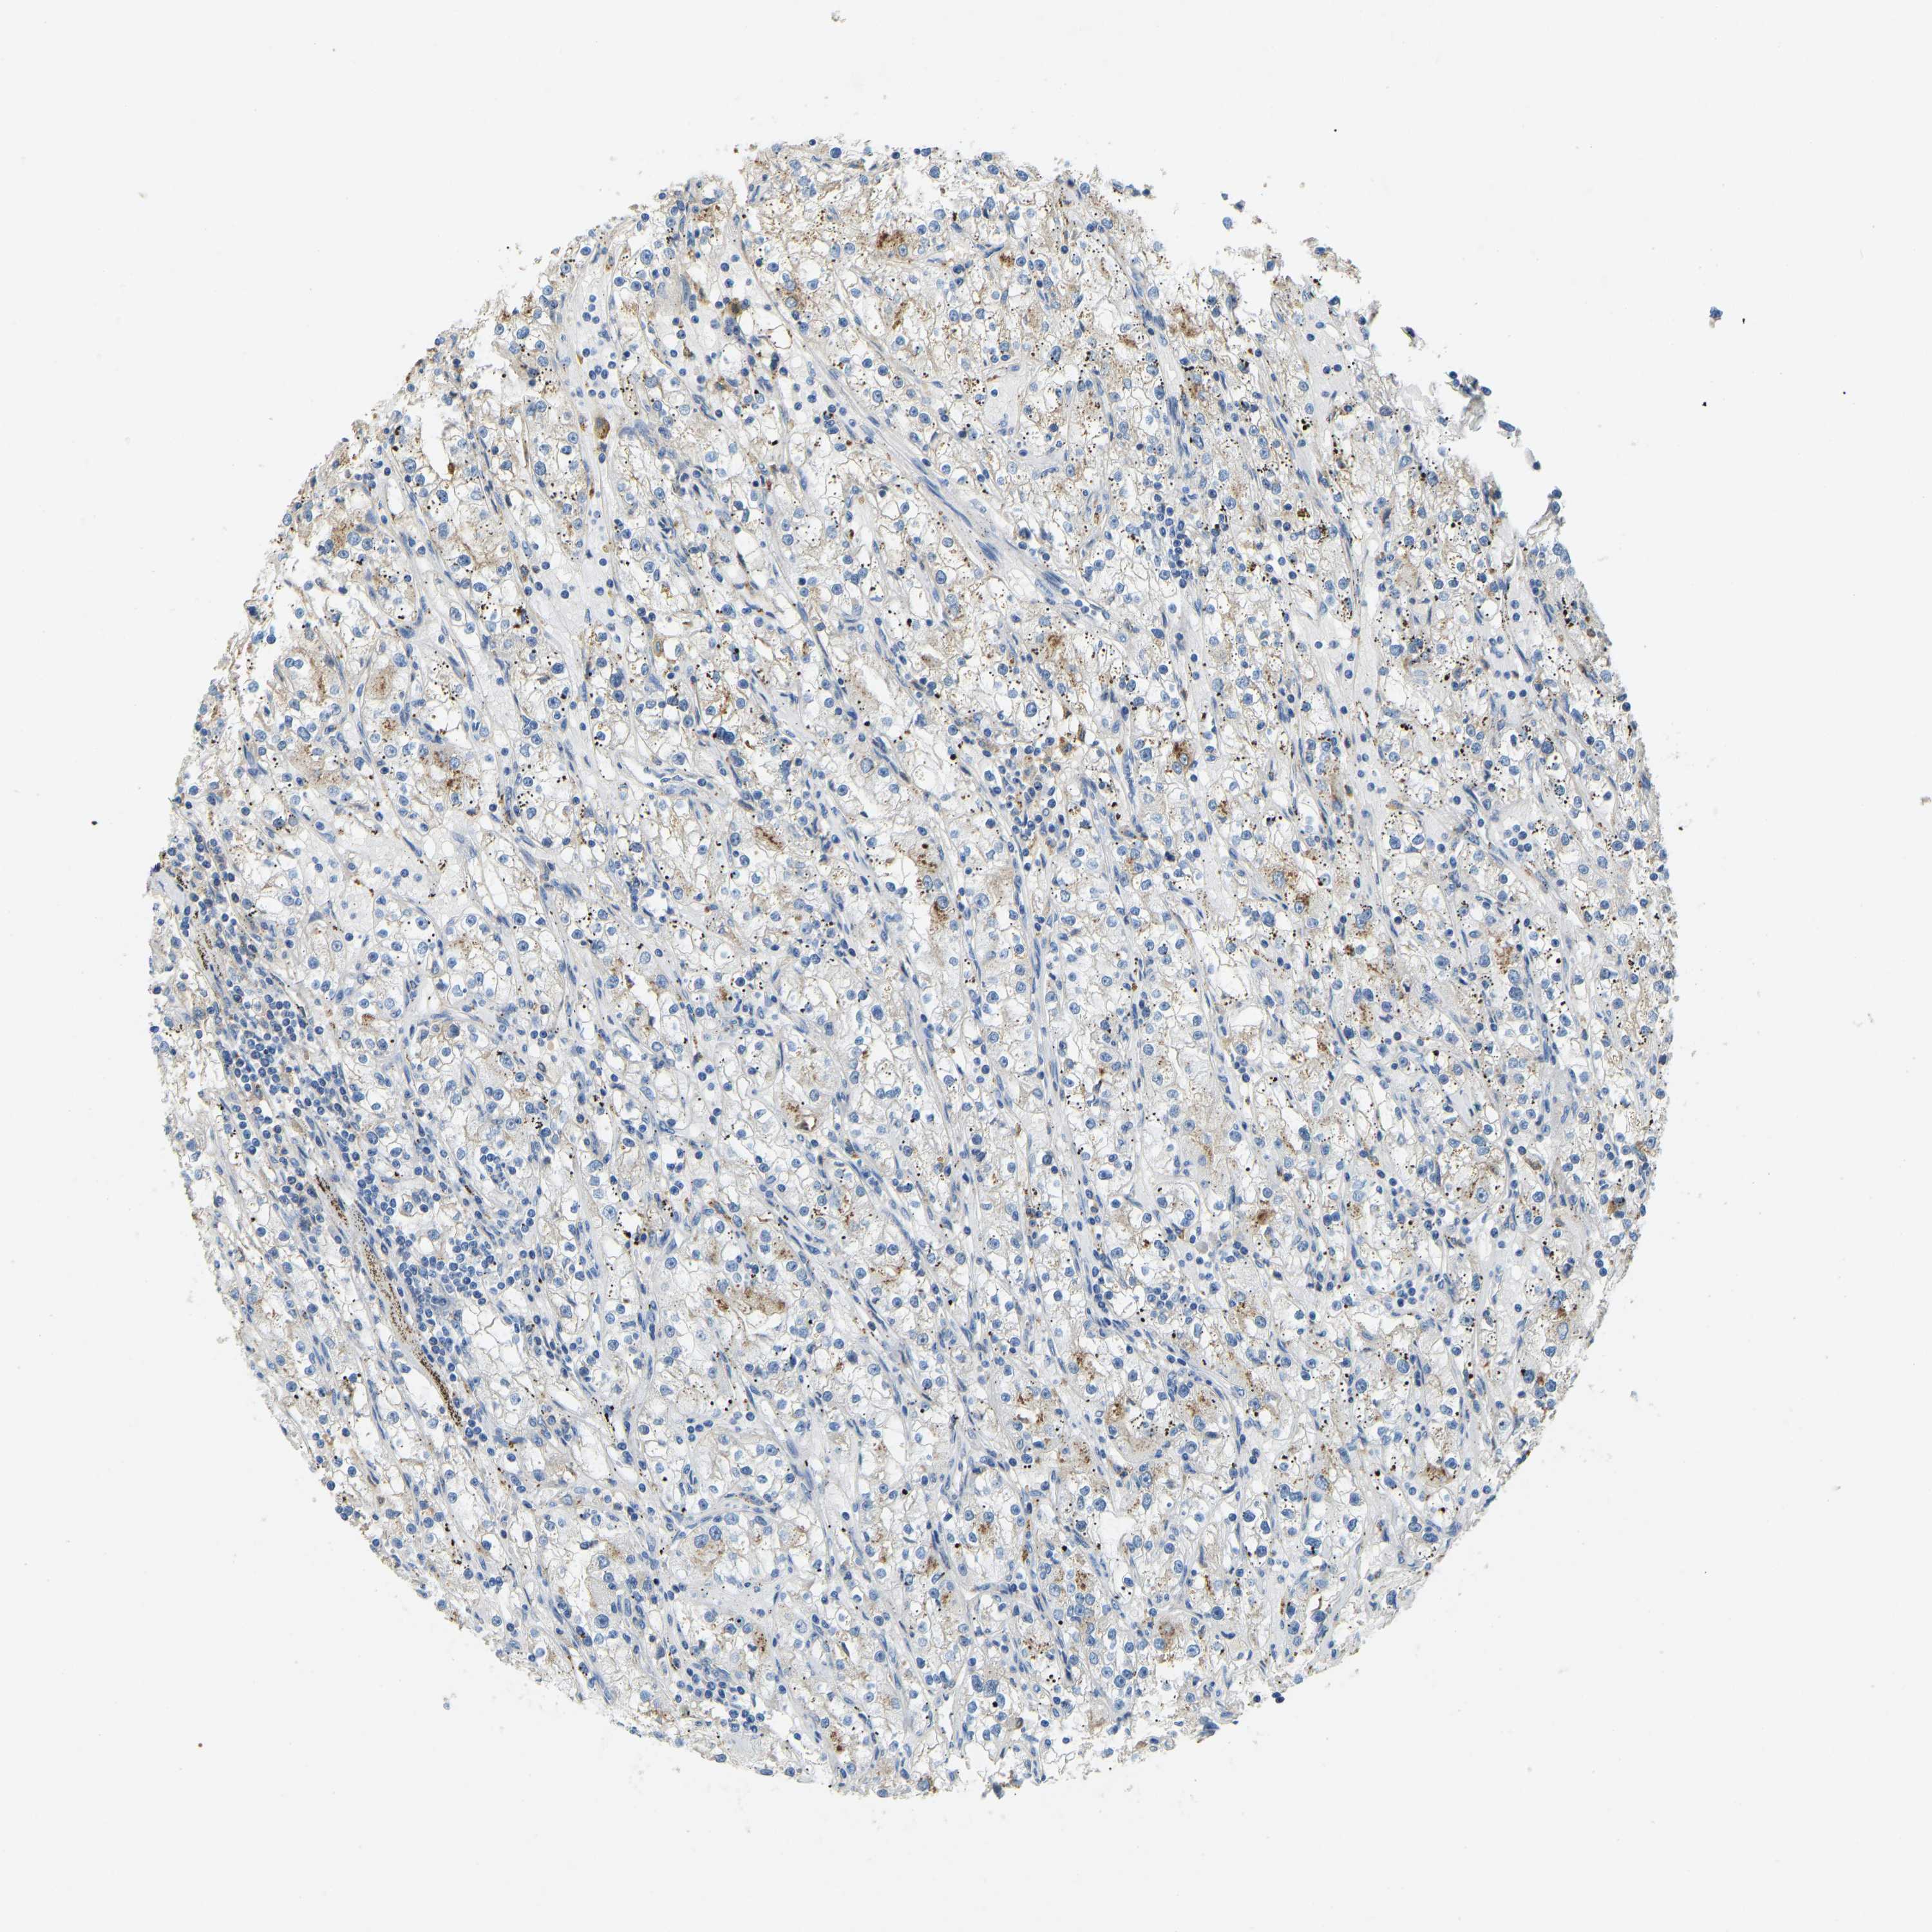

KIDNEY RENAL CLEAR CELL CARCINOMA (VALIDATION) - Interactive survival scatter ploti

The Survival Scatter plot shows the clinical status (i.e. dead or alive) for all individuals in the patient cohort, based on the same data that underlies the corresponding Kaplan-Meier plots. Patients that are alive at last time for follow-up are shown in blue and patients who have died during the study are shown in red.

The x-axis shows the expression levels (FPKM) of the investigated gene in the tumor tissue at the time of diagnosis. The y-axis shows the follow-up time after diagnosis (years). Both axes are complimented with kernel density curves demonstrating the data density over the axes. The top density plot shows the expression levels (FPKM) distribution among dead (red) and alive patients (blue). The right density plot shows the data density of the survived years of dead patients with high and low expression levels respectively, stratified using the cutoff indicated by the vertical dashed line through the Survival Scatter plot. This cutoff is automatically defined based on the FPKM cutoff that minimizes the p-score. The cutoff can be changed by dragging the vertical line or by entering a cutoff value in the square labeled "Current cut-off".

Under the Survival Scatter plot the p-score landscape (black curve; left axis) is shown together with dead median separation (red curve; right axis). Dead median separation is the difference in median mRNA expression between patients who have died with high and low expression, respectively. It is calculated as follows: median FPKM expression of dead patients with high expression - median FPKM expression of dead patients with low expression. This is intended to aid the user in visually exploring custom cutoffs and the associated p-scores and dead median separation.

Individual patient data is displayed and can be filtered by clicking on one or more of the category buttons on the top of the page. Categories describing expression level and patient information include: high, low, alive, dead, female, male and tumor stages. The scale of the x-axis can be toggled between linear and log-scale by clicking on the "x log" button. Mouse-over function shows TCGA ID, patient information and mRNA expression (FPKM) for each patient.

& Survival analysisi

Kaplan-Meier plots summarize results from analysis of correlation between mRNA expression level and patient survival. Patients were divided based on level of expression into one of the two groups "low" (under cut off) or "high" (over cut off). X-axis shows time for survival (years) and y-axis shows the probability of survival, where 1.0 corresponds to 100 percent.

THBS4 is not prognostic in Kidney Renal Clear Cell Carcinoma (validation)

Best expression cut offi

Based on the FPKM value of each gene, patients were classified into two groups and association between prognosis (survival) and gene expression (FPKM) was examined. The best expression cut-off refers the FPKM value that yields maximal difference with regard to survival between the two groups at the lowest log-rank P-value. Best expression cut-off was selected based on survival analysis .

When clicking on this number, the vertical dashed line indicating cut-off, the interactive survival plot, and the Kaplan-Meier curve will be adjusted to show results based on the best expression cut-off.

: 0.41

TCGA RNA samplesi

RNA-seq data is reported as average FPKM (number Fragments Per Kilobase of exon per Million reads), generated by the The Cancer Genome Atlas (TCGA) .

Normal distribution across the dataset is visualized with box plots, shown as median and 25th and 75th percentiles. Points are displayed as outliers if they are above or below 1.5 times the interquartile range. FPKM values of the individual samples are presented next to the box plot.

Average pTPM 3.2

Number of samples 100